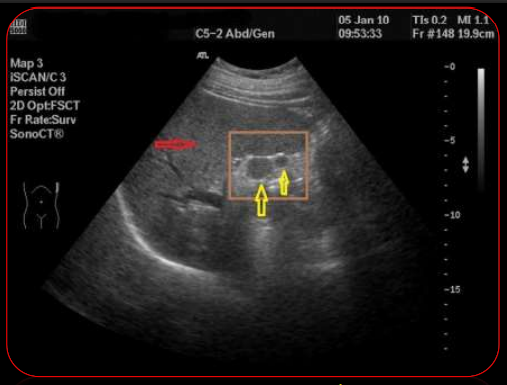

<p>Qué artefacto es más evidente?</p>

Qué artefacto es más evidente?

Sombra acústica posterior

¿Qué artefacto es util para la detección de cálculos?